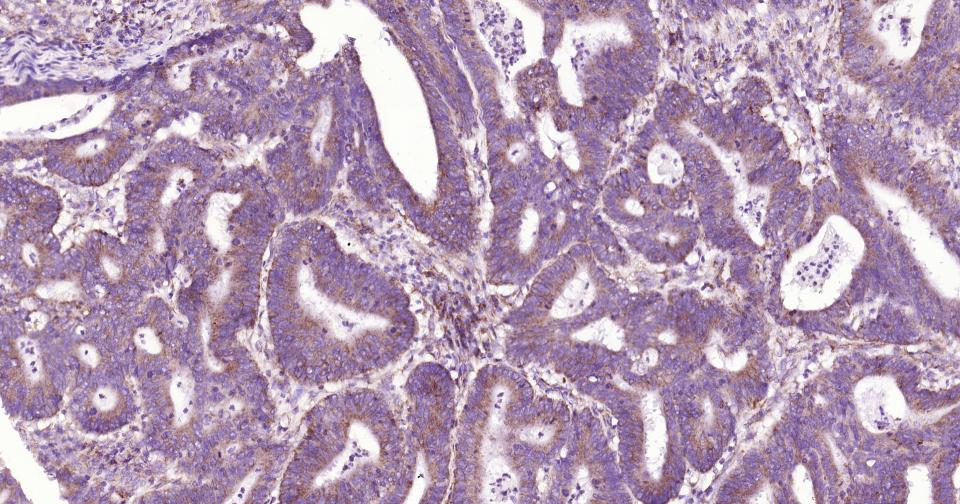

Paraformaldehyde-fixed, paraffin embedded Human Colon Cancer; Antigen retrieval by boiling in sodium citrate buffer (pH6.0) for 15 min; Antibody incubation with AIF Monoclonal Antibody, Unconjugated(bsm-34316R) at 1:200 overnight at 4°C, followed by conjugation to the SP Kit(Rabbit, SP-0023) and DAB (C-0010) staining.